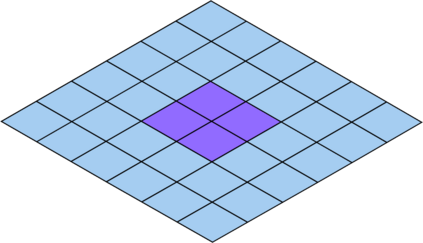

Deep Convolutional Neural Networks (DCNNs) are used extensively in biomedical image segmentation. However, current DCNNs usually use down sampling layers for increasing the receptive field and gaining abstract semantic information. These down sampling layers decrease the spatial dimension of feature maps, which can be detrimental to semantic image segmentation. Atrous convolution is an alternative for the down sampling layer. It increases the receptive field whilst maintains the spatial dimension of feature maps. In this paper, a method for effective atrous rate setting is proposed to achieve the largest and fully-covered receptive field with a minimum number of atrous convolutional layers. Furthermore, different atrous blocks, shortcut connections and normalization methods are explored to select the optimal network structure setting. These lead to a new and full-scale DCNN - Atrous Convolutional Neural Network (ACNN), which incorporates cascaded atrous II-blocks, residual learning and Fine Group Normalization (FGN). Application results of the proposed ACNN to Magnetic Resonance Imaging (MRI) and Computed Tomography (CT) image segmentation demonstrate that the proposed ACNN can achieve comparable segmentation Dice Similarity Coefficients (DSCs) to U-Net, optimized U-Net and hybrid network, but with significantly reduced trainable parameters due to the use of full-scale feature maps and therefore computationally is much more efficient for both the training and inference.